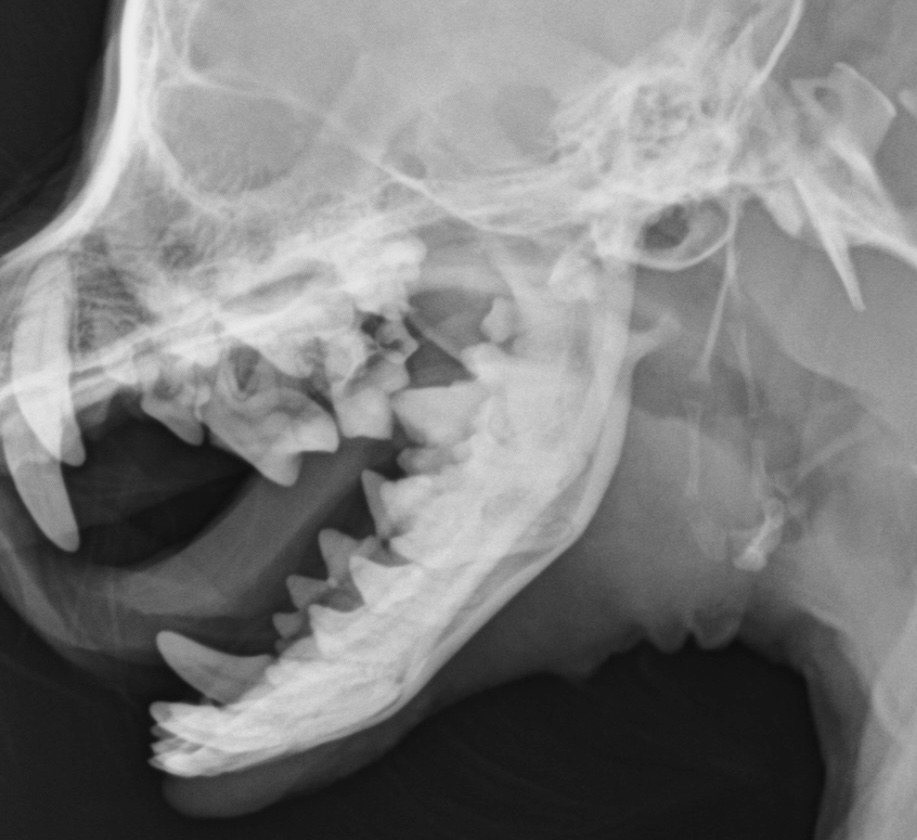

歯石の付着状況や歯周病の進行度合いを確認し、必要に応じて頭部のレントゲン撮影も実施します。

▲ 頭部のレントゲン検査